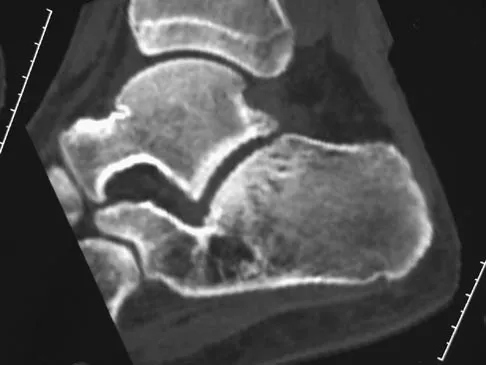

A 17-year-old patient sustained a closed calcaneal fracture when he jumped off of a roof 2 years ago, and he underwent nonsurgical management at the time of injury. The patient now reports lateral hindfoot pain that is worse with weight-bearing activities. Anti-inflammatory drugs and orthoses have failed to provide relief. Coronal and sagittal CT scans are shown in Figures 36a and 36b. What is the best course of action?